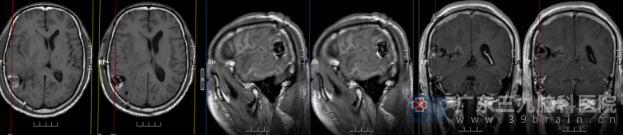

术后头颅MR检查提示: 1.右侧颞枕叶-脑室后角占位切除术+脑室外引流术后改变,占位性病变已切除,术道及术区混合积液、积气; 2.右侧海马钩回疝、右侧大脑镰下疝较前减轻;左侧侧脑室扩大伴间质性水肿较前有所缓解;